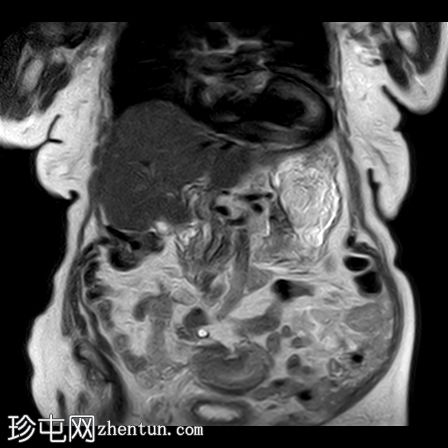

矢状位

T2

1.jpg

子宫呈U形,宫底轮廓消失,宫底突出至扩张的阴道内,宫颈位于内翻的宫底上方(II级子宫内翻):

宫底处可见阴道内可见边界不清、分叶状实性肿块,明显扩张阴道壁,阴道壁完整。

肿块最大轴向及头尾径约为 9.7 x 9.6 x 9.5 cm,T1 加权像呈低信号,T2 加权像呈中/高信号,伴有扩散受限和不均匀增强。

矢状位MRI:显示子宫呈U形,正常的凸形宫底轮廓消失。